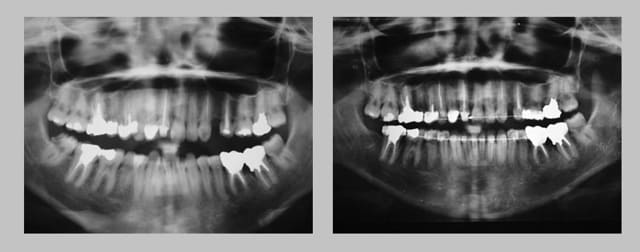

Pano 1 whnhsx - Eugenol